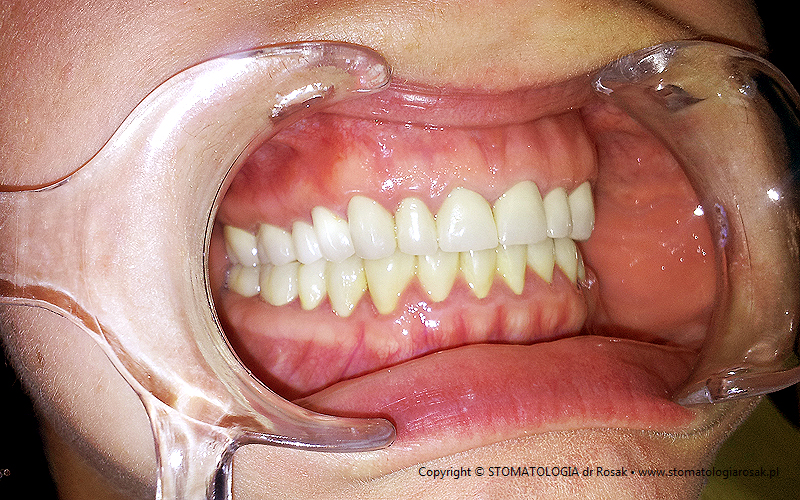

2. Pacjent z licznymi wypełnieniami (plombami), zgryzem głebokim, zaburzona estetyka

i funkcja układu narządu żucia (diastema).

| 2a. Pacjentka przed leczeniem |

2b. Gotowe mosty pełnoceramiczne

na podbudowie cyrkonowej |

2c. Gotowe mosty i korony pełnoceramiczne

2d. Gotowa praca stała - korony pełnoceramiczne